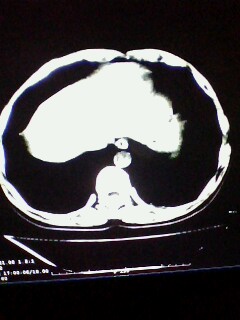

标题: CT28315:咳嗽咳痰咯血半月并胸痛 [打印本页]

标题: CT28315:咳嗽咳痰咯血半月并胸痛

1、纵膈窗效果不好,初步考虑左肺下叶感染性病灶,建议正规抗炎治疗后复查   2、右肺下叶陈旧性病灶伴局部胸膜增厚。

考虑左肺下叶周围型肺癌.图象欠清,请问病人贵更?

考虑左肺下叶周围型肺癌.

图像资料欠清,建议强化,考虑周围型肺癌。

左下肺肿块影,深分叶,考虑肺癌。

左下肺球形病灶,考虑:1:球形肺炎;2:周围型肺癌不除外,建议治疗后复查

不排除左肺下叶周围型肺癌可能!建议穿刺活检!

考虑左肺下叶周围型肺癌并阻塞性肺炎。